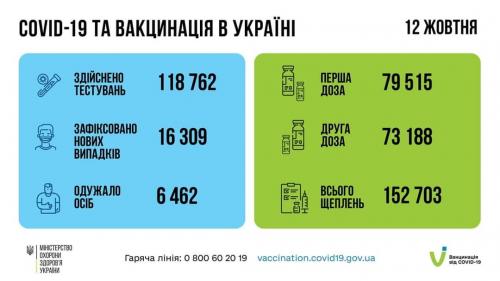

МОЗ: Уперше з початку пандемії було зроблено понад 100 тисяч ПЛР-досліджень за добу

03.02.2022 12:10